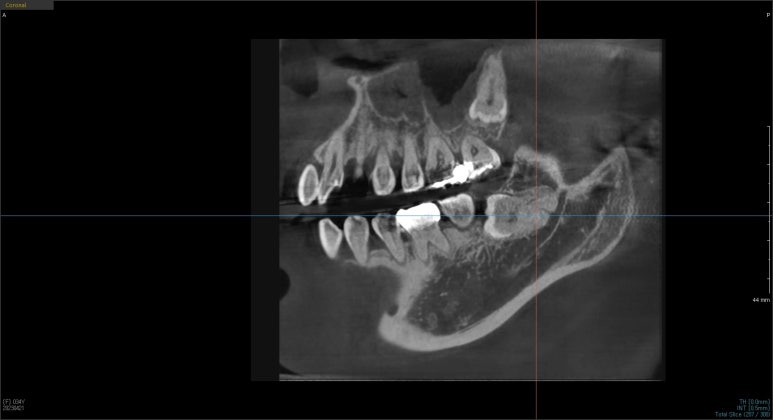

또한 신경관과 닿아있을 가능성이 있는 경우에는 추가적인 CT 촬영을 통해 신경관과 닿아있는지 여부를 확인해야 합니다.

신경관과 사랑니 뿌리가 닿아있는지 확인하기 위한 CT촬영 예시

신경관과 닿아있지 않은 경우라면 잇몸을 절개해 치아를 분할해서 발치할 수 있는데요.

안타깝게도 사랑니 뿌리가 신경관과 닿아있다면 일반적인 치과의원에서는 발치가 어려울 수 있어

대학병원 또는 사랑니발치만 전문으로 진행하는 치과로 발치를 의뢰하기도 합니다.